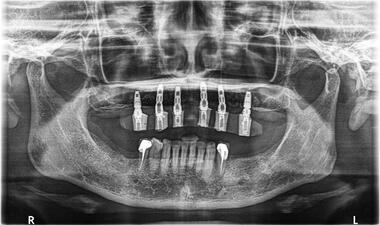

術中

上顎缺牙,植入六顆植體